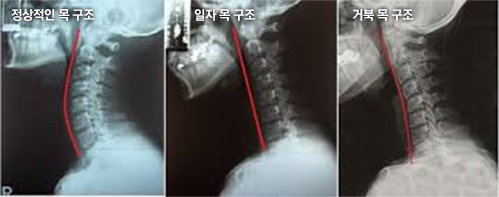

대개는 퇴행성변화가 진행되면서 발생하는 경우가 많습니다만 현대인들의 잘못된 자세와 습관이 장기적으로 이어지면서 목뼈의 정렬상태가 변형이 오면서 목디스크 환자 발생이 점차 늘어가고 있습니다.

목 디스크의 구조